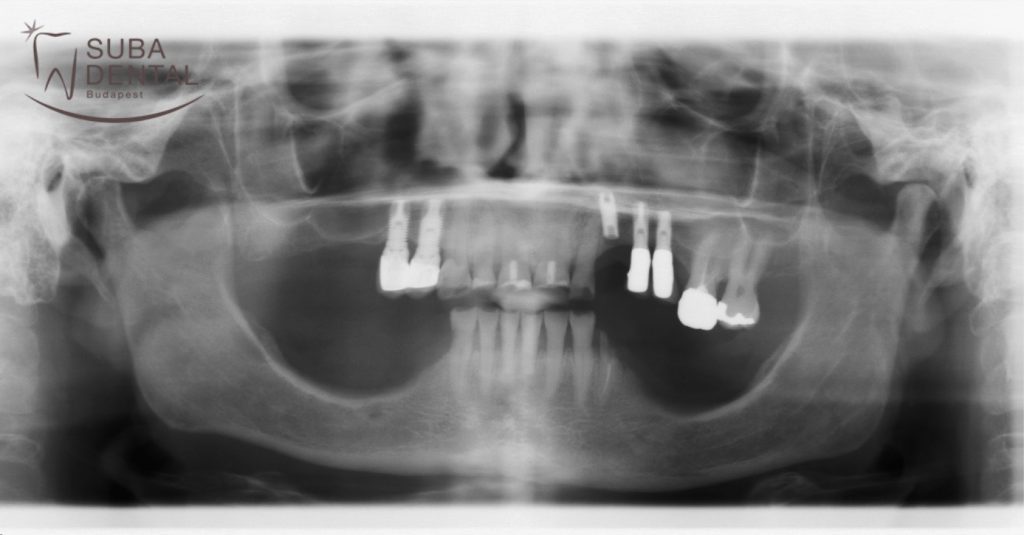

Az első találkozás alkalmával a páciens hozta, az általa készíttetett panoráma röntgenjét, melyen látszott, hogy az összes felső fogát koronázni kell. Szerencsére minden meglévő foga és az implantátumok is jó állapotban vannak, így nem kellet fogat/implantátumot eltávolítani. Az implantátumokat régen, egy másik rendelőben ültették be. Mivel páciensünk újabb implantátumok behelyezését nem szeretné, így egy kombinált munkát javasoltunk a számára az alsó állcsontra ahol, az összes őrlő és kisőrlő fogat pótolni kellett. Ez a megoldás rokonszenvessé is vált számára és el is fogadta ezt a kezelési tervet. Így tehát a felső fogakra rögzített megoldást és az alsókra kombinált munkát (fix híd fogsorral kombinálva) készítünk.

Első panoráma röntgen, amellyel a páciens érkezett (kiinduló állapot).